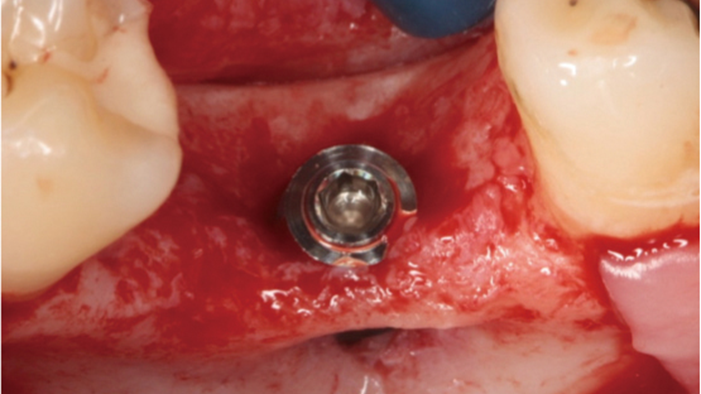

Clinical case: Delayed implant placement: sinus floor elevation by means of lateral

approach & implant placement with GBR

- Courtesy of Dr. Irfan Abas, Netherlands -